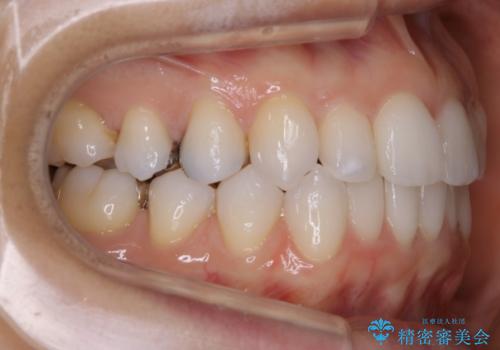

歯のガタつきをとるためのスペース作りの方法の一つにディスキング(IPR)という方法があります。

歯と歯の間を一ケ所あたり最大0.5mmまでの範囲内で削ることで歯自体が少し小さくなり、それにより作られるスペースを数ヶ所分合わせることで合計で数mmの大きなスペースが作れるという方法です。

当院ではなるべく歯の機能や見た目に影響の出ないよう、作業時に拡大鏡の使用や削るタイミングの微調整を行っています。